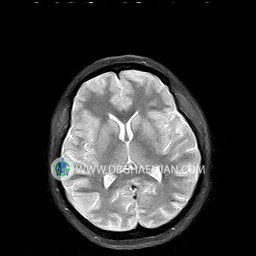

پزشکان اغلب از تصویربرداری ام آر آی برای تشخیص و درمان عارضه های پزشکی که فقط با استفاده از اشعه ایکس یا میدان مغناطیسی و امواج رادیویی قابل مشاهده است، استفاده می کنند. دستگاه ام آر آی تصاویر دقیق از ساختار های داخلی بدن ایجاد می کند. در این کیس نوریت اوربیت چب و سلای خالی بیمار مشاهده می شود.

– Small fluid around the left optic nerve with mild edema suggestive for left optic neuritis

– Extension of suprasella cistern to sella with thin pituitary gland in floor of sella ( empty sella )

are seen